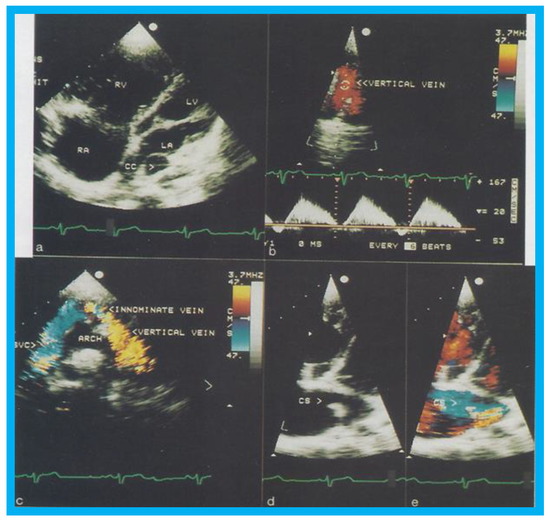

Total anomalous pulmonary venous connection (TAPVC) is an uncommon congenital heart defect (CHD) constituting approximately 1% of all CHDs. On the basis of site of drainage of the pulmonary veins, the TAPVC patients are classified into supra-cardiac, cardiac, infra-cardiac, and mixed types. The mixed type of TAPVC comprises 5% to 10% of all TAPVCs. We presented echocardiographic and angiographic findings of two cases of mixed TAPVC, with the intent of highlighting the limitations of echocardiography in comprehensive assessment of this rare anomaly [8]. Following echocardiographic and angiographic studies, both children underwent successful surgical correction of their respective defects.

Transthoracic echocardiogram in case 1 showed dilated right atrium (RA) and right ventricle (RV) with a common pulmonary venous confluence (Figure 6a) and a vertical vein emptying into the innominate vein and superior vena cava (SVC) (Figure 6b,c). Dilated coronary sinus (CS) with mosaic color-Doppler flow pattern of pulmonary venous entry was also seen (Figure 6d,e). These findings indicated mixed type of total anomalous pulmonary venous connection. The findings in case 2 were very similar to those seen in case 1. However, not all pulmonary veins were identified and their course and connections to the pulmonary venous confluence could not be established. Therefore, catheterization and cineangiography were undertaken to validate the diagnosis prior to corrective cardiac surgery. Levo-angiographic frames following right pulmonary artery cineangiogram demonstrated entry of right pulmonary veins into the coronary sinus in both cases (Figure 7a,b,d). Direct injection into the left pulmonary vein via a catheter positioned into it via the innominate and vertical veins in the first case (Figure 7c) and on levo-angiogram following left pulmonary artery cineangiogram in the second case (Figure 7e) clearly demonstrated left pulmonary venous drainage via the vertical vein into the systemic venous circuit. Transesophageal echocardiography during surgery in both cases could not delineate the number of pulmonary veins and their connection with the confluence, although we had only access to single-plane TEE probe at that time.

On the basis of the experience in these two cases, we recommended angiographic definition of all pulmonary veins in mixed type of TAPVC at that time [8]. With today’s availability of better echocardiography machines (compared with mid-1990s) and multi-plane transesophageal probes, angiography may not be needed in most patients suspected of having mixed type of TAPVC. Certainly, today’s cross-sectional imaging can define the anatomy in most patients with mixed TAPVC and angiography may not be necessary.

Figure 6. Selected two-dimensional (a) and color flow images (be) of a patient (case 1) with mixed type of total anomalous pulmonary venous connection are shown. In (a), dilated right atrium (RA) and right ventricle (RV) and common pulmonary venous confluence (CC) are illustrated. In (b,c), spectral and color flow images demonstrate the vertical vein draining into the innominate vein and superior vena cava (SVC). In (d,e), dilated coronary sinus (CS) with mosaic color flow pattern of pulmonary venous entry are apparent. ARCH, aortic arch; LA, left atrium; LV, left ventricle. Reproduced from Reddy S.C.B., et al. [8].